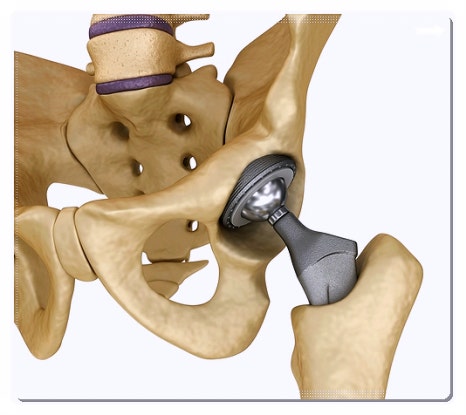

고관절은 우리 몸에서 상체와 하체를 연결하는 중요한 축입니다.

하지만 수술은 손상된 부위를 물리적으로 복구하는 과정일 뿐, 무너진 주변 근육의 균형까지 한 번에 되돌려 주지는 못합니다.

먼저 고관절 문제를 단순히 뼈의 문제로만 보지 않는 것이 필요합니다.

고관절을 둘러싼 근육과 힘줄, 그리고 이를 관장하는 기혈의 흐름까지 종합적으로 살펴보아야 합니다.

수술 부위의 염증을 완화하는 것도 중요하지만, 수술로 약해진 주변 조직을 강화하여 재발을 예방하는 것이 핵심입니다.

그래서 엑스레이 등을 통한 정밀 진단으로 현재 골격 상태를 확인하는 동시에,

한의학적 관점에서 골반의 균형을 바로잡는 부분도 함께 고려하게 됩니다.

또한 개인별 증상에 맞춘 재활 프로그램은 고관절의 가동 범위를 점진적으로 넓혀주는 데 도움을 줄 수 있습니다.